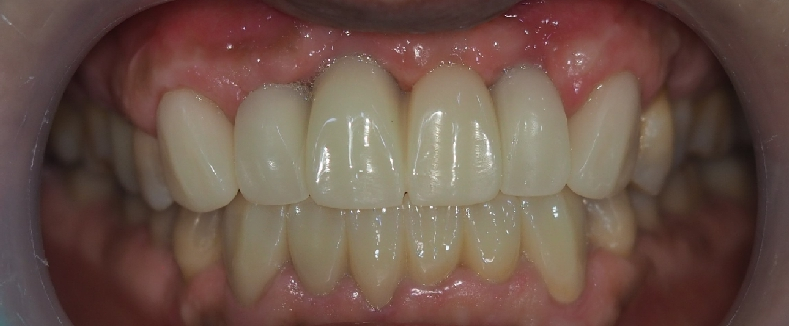

최종 보철 사진입니다.

위의 핑크 레진 부분은 치아가 너무 길어 보이지 않게 환자분의 잇몸에 맞춰 제작 되었습니다.

육안으로 보면 티가 이 사진 보다 많이 나지 않습니다!